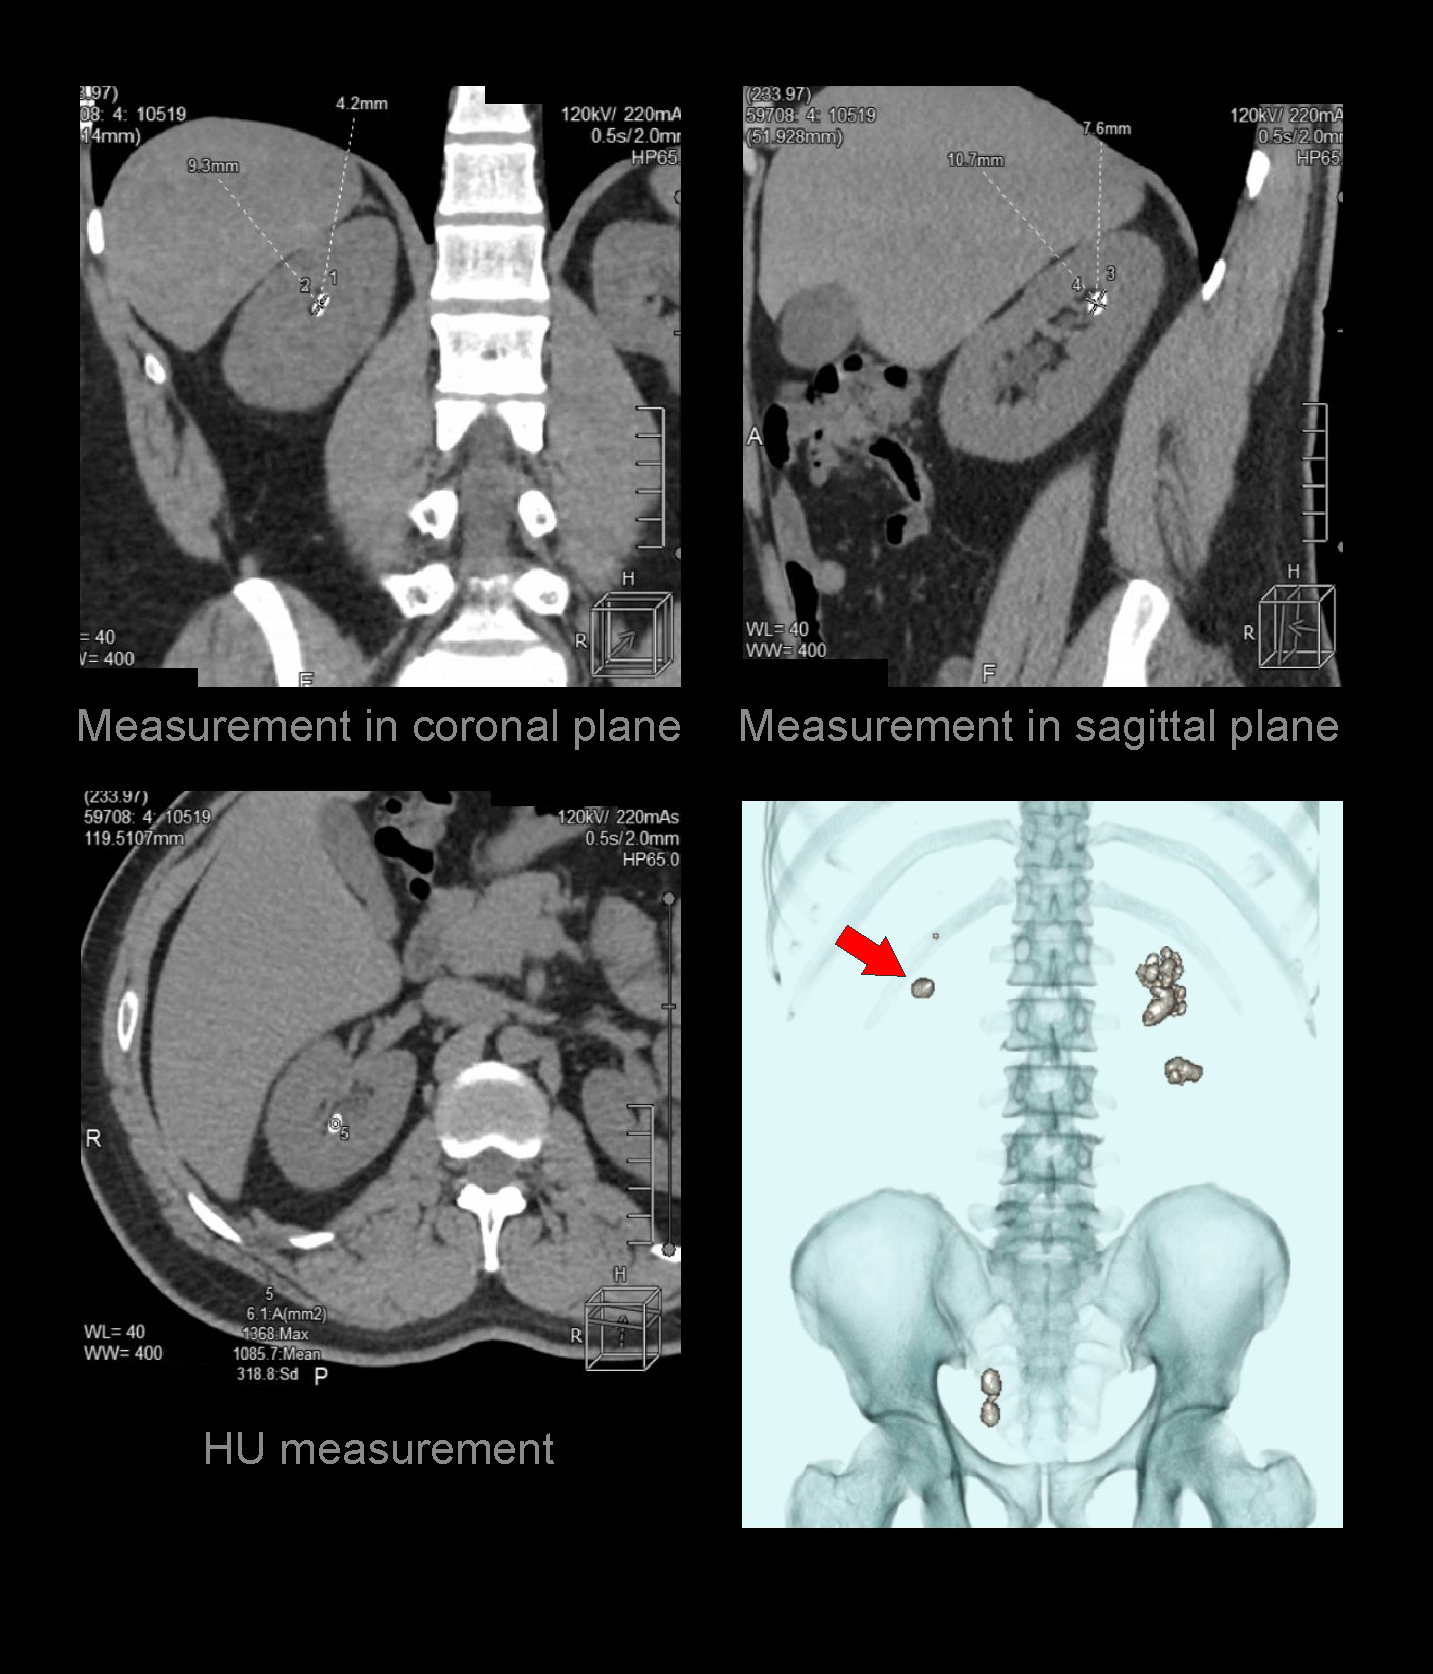

- Layered 3D images to show stones with respect to the lumbar spine.

- Measurements in length and width of each calculus.

- Measurement in Hounsfield unit (HU) of each calculus.